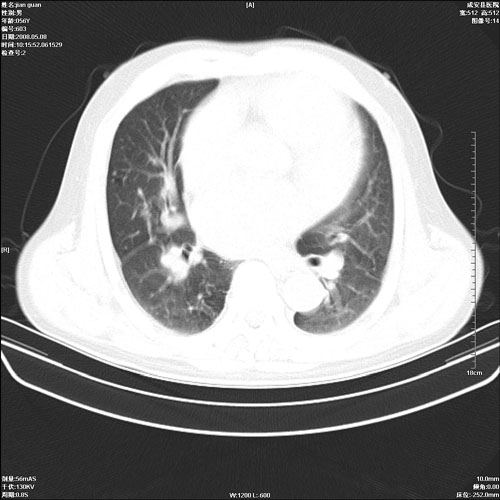

病人 男 60岁 主诉 胸闷 无明显发热 一般情况尚可。

两上肺陈旧性结核;慢支肺气肿、伴感染?

两上肺陈旧性结核;慢支肺气肿

1.两上肺陈旧性结核;慢支肺气肿。

考虑.两上肺陈旧性结核;慢支肺气肿。肺心病

两上肺陈旧性结核,慢支肺气肿。

两上肺陈旧性结核;慢支肺气肿。肺肺间质纤维化

两上肺陈旧性结核;慢支肺气肿。

1.陈旧肺结核;

2.慢支肺气肿;